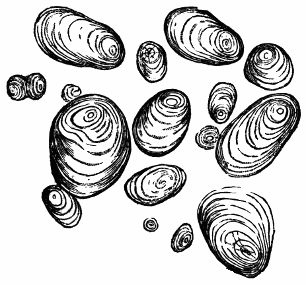

IPECACUAN′HA. Syn. (Ipecacuanha, L.; Ipecacuhan, E., B. P.) Radix ipecacuanhæ, Ipecacuanha (Ph. L. E. & D.), L. The dried root of Cephaëlis Ipecacuanha, or the true ipecacuanha plant, one of the Cinchonaceæ. “Ashy coloured, tortuous, very much cracked, and marked in rings with deep fissures, having an acrid, aromatic, bitterish taste.” (Ph. L.) It occurs in pieces 3 or 4 inches long, and about the size of a writing quill.—Dose. As an emetic, 10 to 20 gr., assisted by the copious use of warm water; as a nauseant, 1 to 3 gr.; as an expectorant and sudorific, 1⁄2 to 1 gr. It is undoubtedly the safest and most useful medicine of its class. It has recently been highly recommended in dyspepsia, combined with other bitters or aperients. Almond meal is sometimes used as an adulterant in ipecacuanha powder.